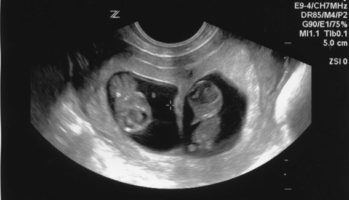

February 6, 2018 متى تظهر علامات الحمل بتوأم؟

تتساءل كثير من الحوامل لأول مرة: هل هو حمل بتوأم؟ وعلى الرغم من أن الإجابة الحاسمة على هذا السؤال…